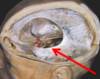

33

What type of hameotoma is depicted? Epidural haematoma (EDH) Subdural haematoma (SDH) Subarachnoid haematoma (SAH) Intracerebral haematoma (ICH)

**Intracerebral haematoma (ICH)**